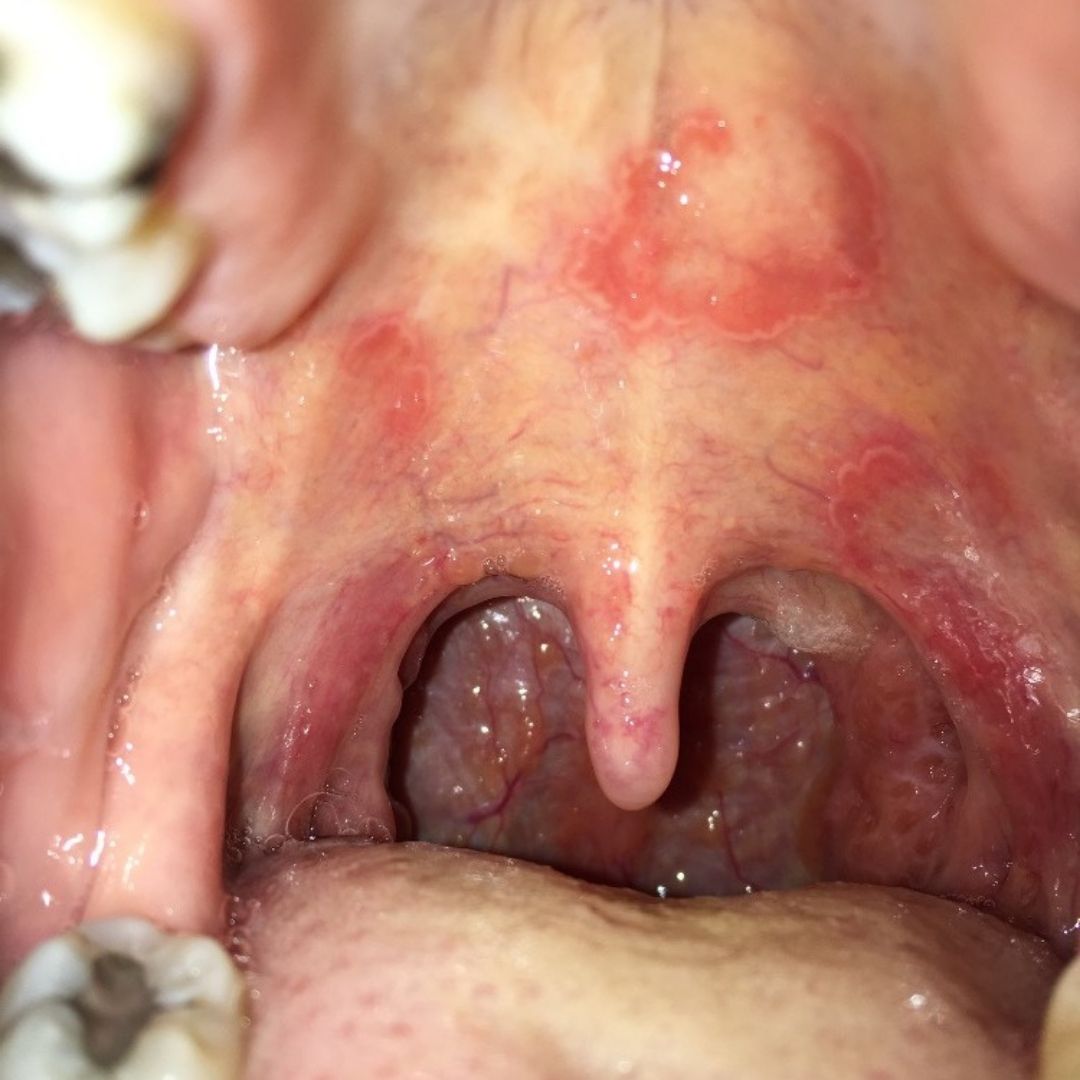

Můj dotaz je následující. Už několik let se mi v puse na horním patře, někdy i na dásních, tvoří takové bílé/červené fleky. Začínalo to jedním kolečkem, které se postupně zvětšuje, až zmizí. Následně se mi jich začalo dělat i více najednou. Vždy cítím, když se mi v puse objeví. Nebolí. Nesvědí. Ale cítím, že je v puse mám. Většinou jsem v tu dobu taky hrozně unavená a cítím se jakoby na teplotu. Vypozorovala jsem, že se mi většinou tvoří po skladkém. Byla jsem u několika doktorů - praktit, zubař, ORL, infekční … Dělali mi krevní testy, testy na syfilis, fotili si mě, dokonce mi vyřezali z patra část postižené tkáně na histologii. Výsledek žádný. Vše negativní.

Domnívám se, že jde o lichen ruber planus (na 90%).